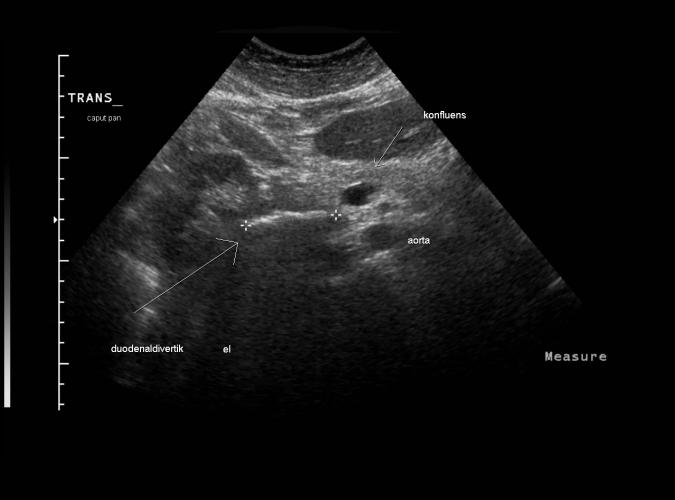

Patienten klagar över tidig mättnadskänsla och "klump i magen". Ultraljud visar enbart duodenaldivertikel (DD).

Trans. caput pancreas med DD mellan kryssen...se bild 4b, 4c